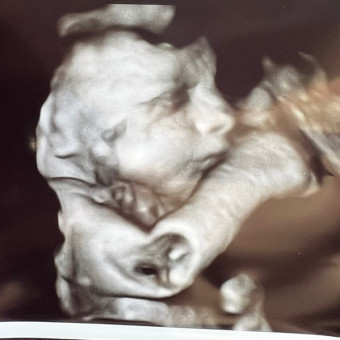

💙🩵 Thoren Andrew Haddad 🩵💙

Ashley Haddad

February 15, 2026